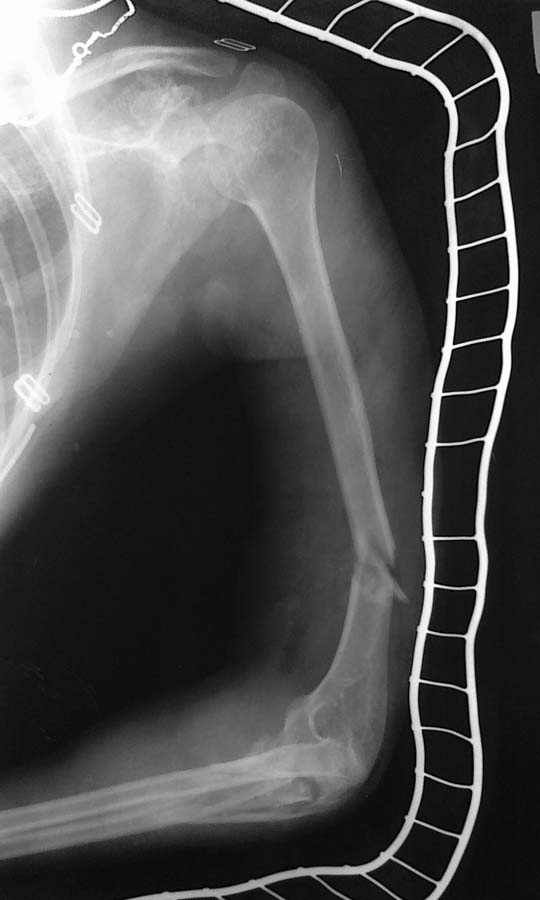

Пациентка А 19 лет. 07.07.12. поступила в ЦГБ с диагнозом: Сочетанная травма. ЗЧМТ. Сотрясение головного мозга. Закрытый оскольчатый перелом н/3 плечевой кости со смещением. Закрытый оскольчатый перелом в/3 лучевой и локтевой кости со смещением. Острая постгеморрагическая ЖДА 2 ст.

Такой перелом плеча можно синтезировать и гвоздем закрыто, и пласиной задним доступом, и аппаратом как циркулярным, так и монолатеральным. Если бы была информация о достуных на месте возможностях, можно было бы более предметно обсудить.

Больше интересует перелом плечевой кости. Можно ли фиксировать блокирующим стержнем, антеградным методом

День добрый, колега! Почему плечо интересует больше? Если предоставить стандартные рентгенограммы плеча и предплечья, то наибольшие проблемы могут возникнуть с локтевой костью....и локтевым суставом в последствии. БИОС плеча оправдан, но нельзя лечить сегмент,забывая о восстановлении функции всей конечности. посмотрите на предплечье, предоставте адекватные рентгенограммы, спросите совета. С уважением Ушаков С.